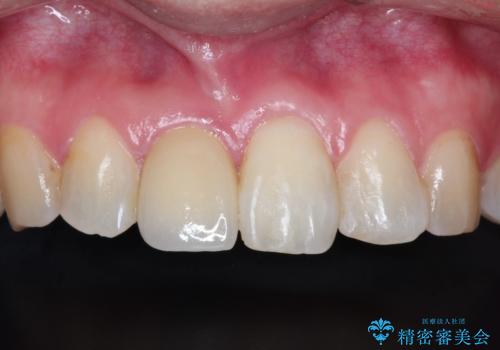

インビザラインにて矯正治療後の前歯のセラミッククラウン治療

- 前歯の歯並びが気になるとのことで来院されました。

右上の1番目の歯が内側に入り込んでしまっており、その歯がの先端がすり減ってしまっていました。

インビザラインによる矯正治療で前歯の歯並びを改善し、セラミッククラウン装着により歯の形態の回復をする計画としました。

矯正とセラミックを併用することで、より完成度の高い状態に仕上げることができました。